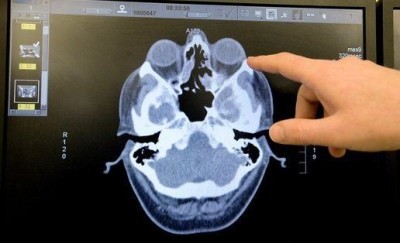

кт носаЕсли принято решение лечить рак носа хирургически, важной оказывается информация, полученная при помощи КТ и МРТ исследований.

КТ помогает выяснить, какую форму имеет опухоль, а также то, как она расположена в пространстве. Также устанавливается плотность новообразования. При помощи МРТ часто удается диагностировать рак на ранних стадиях.